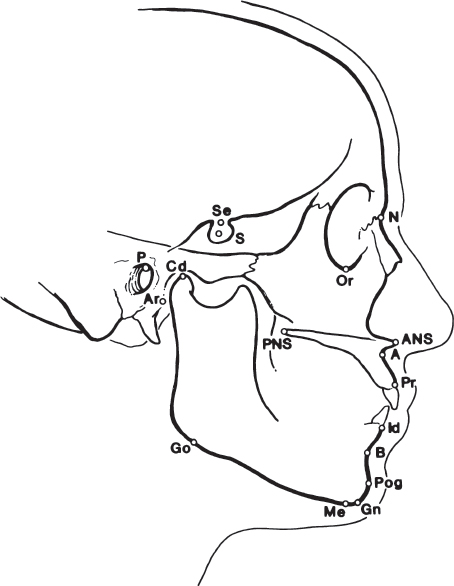

The cephalometric radiograph allows objective evaluation of bony and soft tissue morphology. To effectively use the lateral cephalometric tracing, standardized bony landmark points must be defined. 7 These skeletal landmarks may then be used to derive reference lines and angles ( Tables 70.1–70.3 ).

Linear measurements may be obtained between any two points, and angular measurements are made between three reference points. Various linear and angular analyses are then performed to aid in the diagnosis and treatment of dentoskeletal deformities.

Effective evaluation of the cephalogram depends on accurate definition and localization of bony landmarks. These points may be anatomical or anthropological, and are located on or in the skeletal structures. In contrast, radiologic or constructed reference points are secondary landmarks marking the intersections of X-ray shadows or lines. The points may be unilateral (in the sagittal plane) or bilateral. Bilateral points may be difficult to precisely determine and measure and therefore may result in slight loss of accuracy. The more commonly used skeletal reference points in cephalometric analysis are seen in Table 70.2 and Fig. 70.9 .

These reference points can be used to construct numerous reference lines, as described in Table 70.1 ( Fig. 70.10 ). Different lines are used for different linear analyses, with one particular line representing the reference plane on which the whole analysis is based. The Frankfort horizontal plane is based on a line joining the superior border of the bony external auditory canal with the inferior border of the infraorbital rim. The Frankfort plane is used as a reference when orienting medical photographs of patients. This plane should be oriented parallel to the floor with the patient in the upright position. However, the Frankfort plane is not usually used for cephalometric analysis because it is based on points that are not midline. As such, they are subject to error. The line connecting the nasion (N) and sella (S) is midline, and it is often used as the reference plane on which most cephalometric analysis is based.

Angles SNA, SNB, and ANB are relatively simple to determine and provide valuable basic information in analyzing the relationship of the maxilla and mandible. These angles have a narrow range of normal values 3 , 8 ( Fig. 70.11 ). If the angle ANB is greater than 4 degrees, a skeletal class II malocclusion is present. The maxillary versus mandibular contribution to this malocclusion may be determined by measuring the angles SNA and SNB. If ANB is greater than 4 degrees and SNA is greater than normal, the class II malocclusion is most likely secondary to maxillary protrusion. If ANB is greater than 4 degrees and SNA is less than normal, mandibular retrognathia probably exists.

Various linear distances have also been described ( Table 70.5 ). Again, these lines are measured by identifying the two connecting points on the cephalometric radiograph. The mandibular base is determined by measuring the distance between the gonion (Go) and pogonion (Pog) when projected onto the mandibular plane. The maxillary base is measured from the posterior nasal spine (PNS) to point A. The distance from the sella (S) to the nasion (N) is the anteroposterior extent of the anterior cranial base.